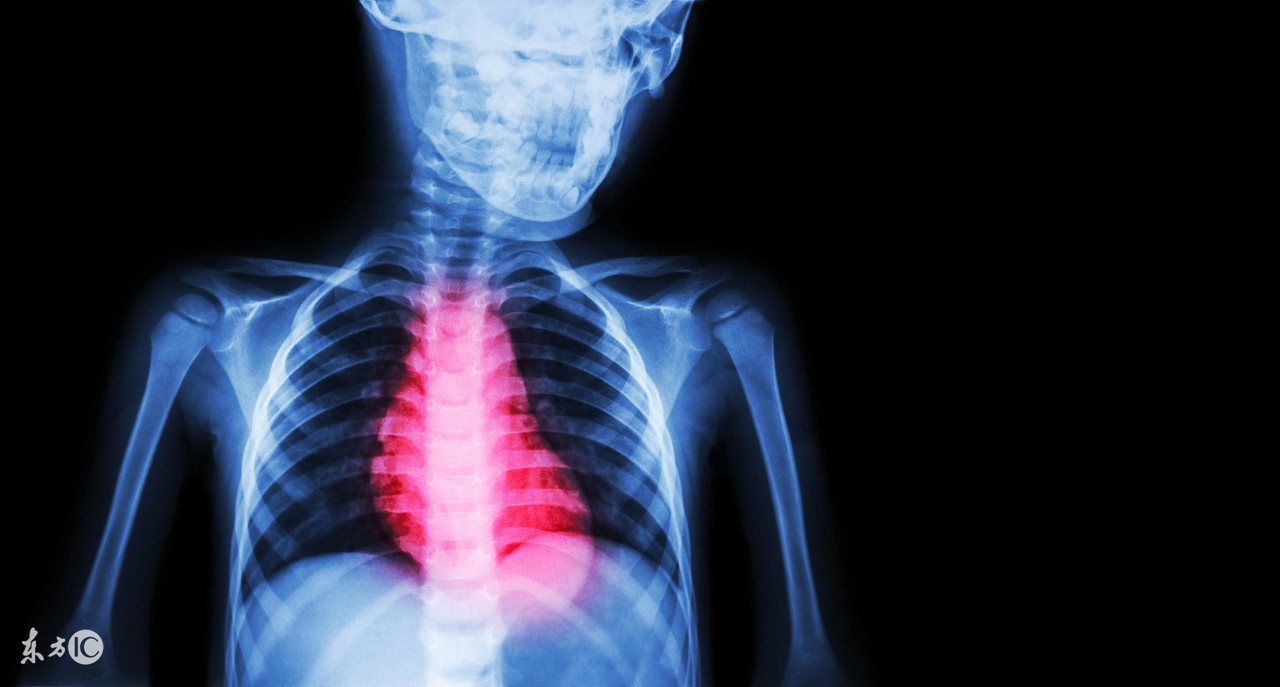

患有心肌缺血的患者朋友在活动量较大或是神经紧张的时候,身体会出现胸闷的情况的,会感觉呼吸不上来,有的时候会有紧缩的疼痛感,还会出现莫名的心悸心慌感的。会有突发心动过缓或是晕厥现象。另外心肌缺血还会有发生心肌梗塞和猝死的危险,因而,因此我们要了解一些关于心肌缺血治疗方面的知识才行的。

第一招、积极治疗:因为心肌缺血对人身体危害很大,且该疾病多发生在老年人身上,老年人身体机能各方面能力降落,患病后十分危险,因此我们要在发现一些心肌缺血症状时及时的去医院治疗。心肌缺血治疗主要是以扩张血管、改善心脏供血为主要。